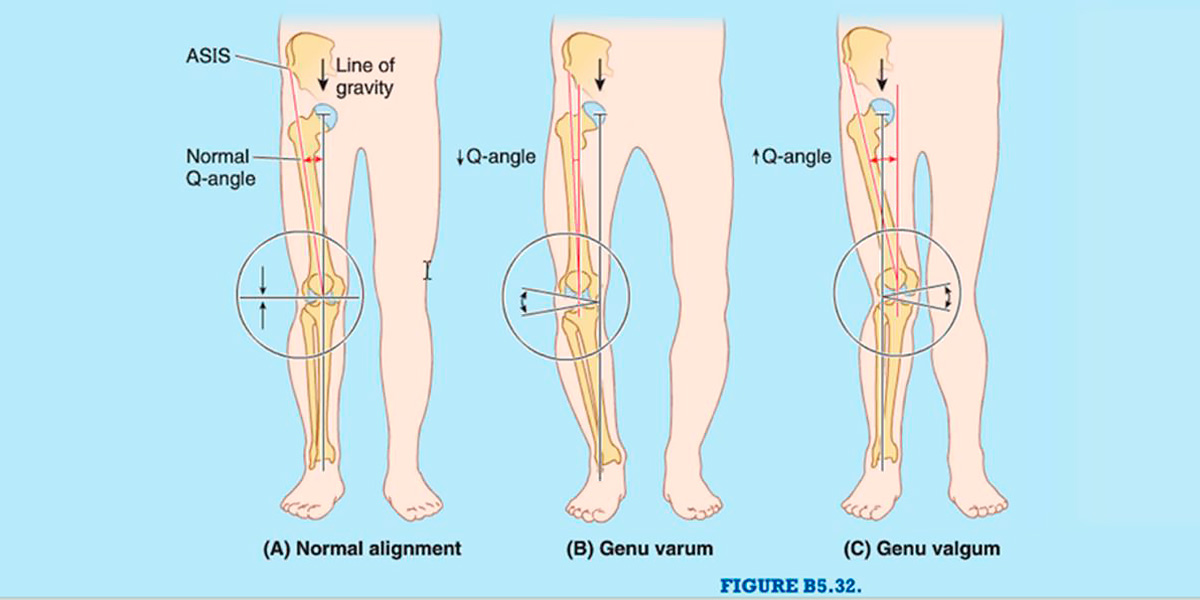

No entanto, por vezes o diagnóstico não é assim tão simples, uma vez que os desequilíbrios na produção de força nos diferentes músculos que constituem o quadríceps também podem alterar a rótula e causar o efeito de desvio patelar.

Figura VII. Representação gráfica dos diferentes graus do ângulo Q e as suas consequências sobre o deslocamento do joelho.

Denomina-se por ângulo Q o ângulo que é formado pela linha da espinha ilíaca superior com a parte centrar da rótula, e a linha da parte central da rótula até à tuberosidade da tíbia; e determina o vetor de força do quadríceps (vemos de forma mais clara na imagem seguinte).